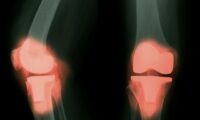

陳氏によると、もしこわばりが長引き、赤み・腫れ・熱感・痛みを伴う場合は注意が必要です。これは一時的な朝のこわばりとは区別すべきであり、関節リウマチやその他の炎症性疾患の可能性を示していることがあります。

• 膝: 慢性的な炎症や関節炎がある人は、睡眠中に関節周囲に水がたまり腫れることで、その周囲の筋肉が緊張し、特に膝に朝のこわばりや不快感が出やすくなります。